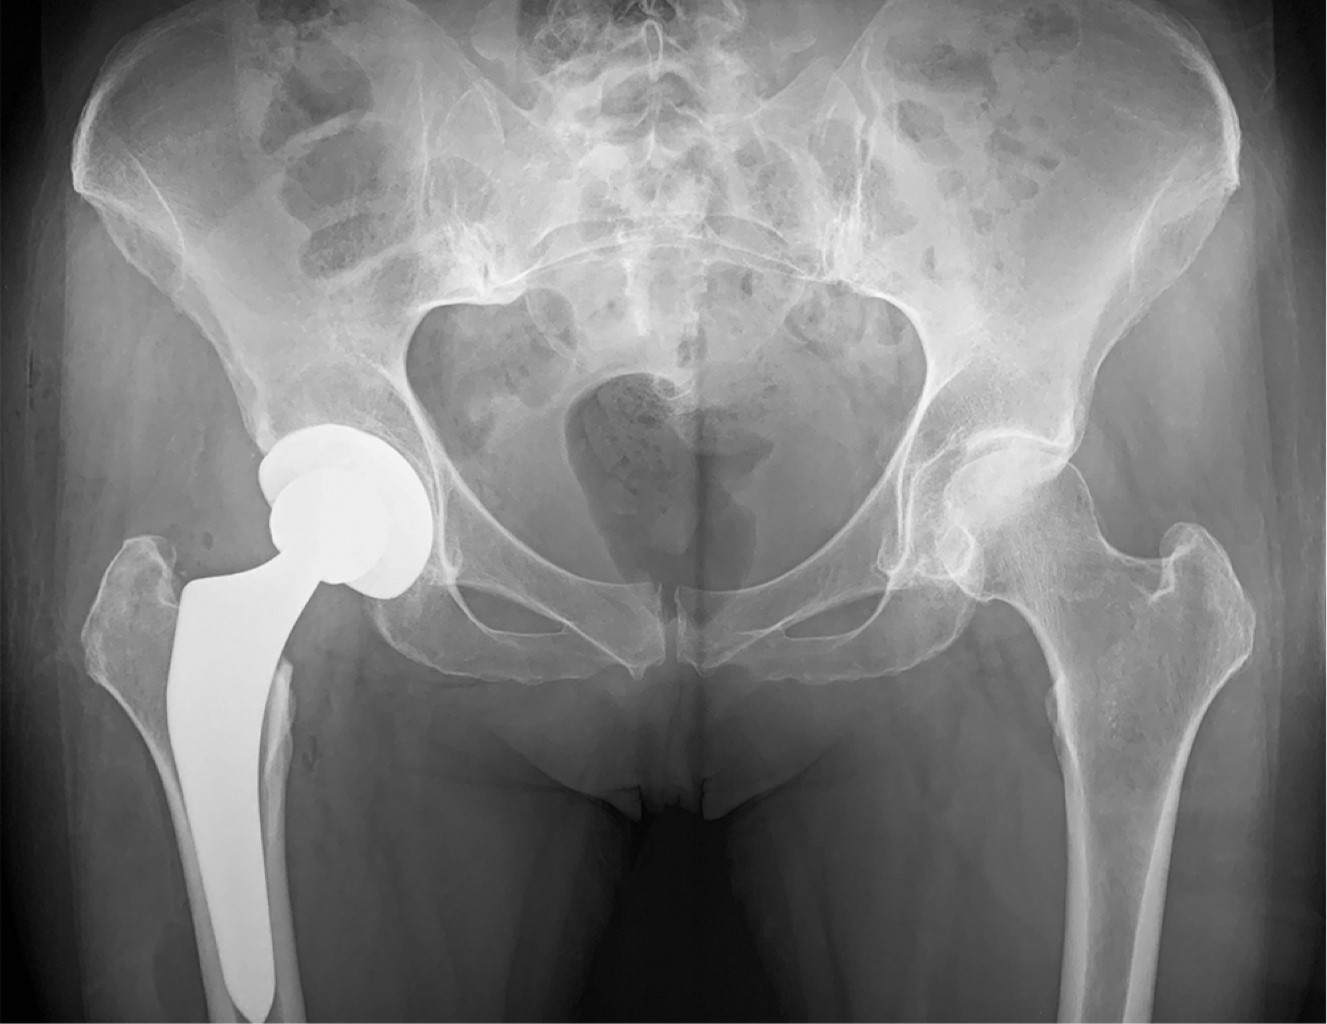

Una vez verificada la estabilidad, se realiza de nuevo rotación externa y una luxación asistida de los componentes, se posiciona de nuevo la extremidad en extensión y rotación externa entre 90 y 110 grados y aducción. Se retira el componente femoral de prueba y se coloca el definitivo, se puede colocar la cabeza definitiva o, a consideración del cirujano, realizar pruebas de nuevo para verificar longitud y estabilidad con cabezas de prueba. Una vez seleccionada la adecuada, se cambia la cabeza de prueba por la definitiva y se realiza de nuevo reducción de los implantes. Se verifica de nuevo la estabilidad de la prótesis realizando movimientos de rotación externa e interna, extensión y flexión (Figura 4).

Se realiza una radiografía de control antes de retirar al paciente de la mesa verificando la posición final de los implantes (Figura 5). Debe tenerse un especial cuidado al retirar al paciente de la mesa quirúrgica, ya que al retirar el poste de la región perineal y desmontar la o las botas, dependiendo de la mesa empleada, el paciente queda sin ningún tipo de sujeción y con el riesgo de tener una caída de la mesa, por lo que no debe descuidarse en ningún momento hasta colocarlo en la cama hospitalaria.